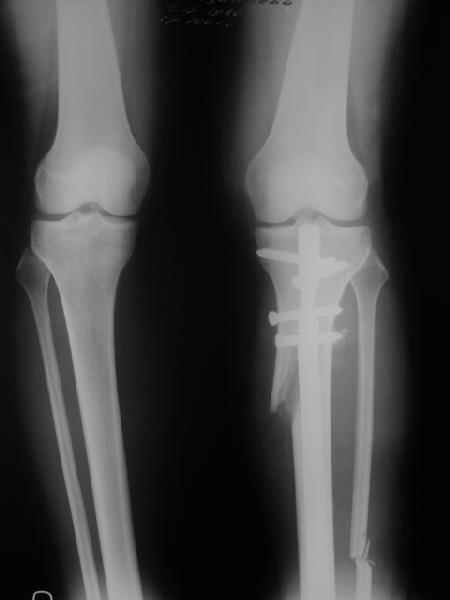

Ещё картинка - схема. Хотя у Соломина всё написано.

Вот ещё картинки, которые отправлял в Ортопод. Коррекция кривизны и удлинение на 3 см.

Снимки в приложении - фас сравнительный с неоперированной ногой. Жду критики.

Впрос про остеотомию большеберцовой непраздный. Эта получилась при надломе несколько более наклонно, чем я делал (сейчас проблема,

как на второй ноге сделать так же). Вот этот высоящий "зуб" центрального отломка не заменит ли в плане косметики то, что получается при медиализации дистального?

Nice job!

It is very interesting to me that as you have derotated the tibia you have centred the patella, I think and the prox tibia looks much more anatomic.

The analysis in the attached images is direct, just using the tools.

Tibial tilt is perhaps more than you want but the tibial correction is to 90 (very slight over

correction.

Will need full length views to tell us about the hka but it appears neutral.

Measurements took 4 mins